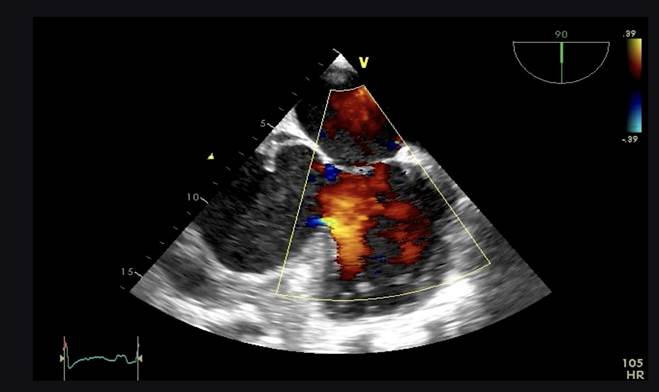

Aproximadamente 3 Semanas posterior al alta presenta cuadro de insuficiencia respiratoria asociado a insuficiencia cardiaca descompensada por lo que acude a nuestro Hospital de Especialidades Abel Gilbert Pontón siendo internada en Unidad Coronaria, a su ingreso se evidencia dolor precordial y torácico bilateral que irradia a región dorsal acompañado de disnea clase funcional NYHA IV/IV, tos persistente y edema leve de miembros inferiores, los laboratorios realizados evidencian anemia leve con hb 10.8 g/dL, péptido natriurético elevado de 12895 pg/ml, enzimas cardiacas negativas, hematuria y proteinuria en uroanálisis; en la radiografía de tórax se muestra cardiomegalia y derrame pleural bilateral; En electrocardiograma taquicardia sinusal, dextrorrotación, complejo QS en cara inferior, sin alteraciones de la onda T y segmento ST. En eco de pleura muestra derrame pleural derecho de moderada a gran cuantía y derrame pleural izquierdo moderado, sospechando de colagenopatía vs enfermedad autoinmune a descartar. Se realiza ecocardiograma transtorácico se evidencia formación aneurismática del VI de 9.5cm x 9.7cm tapizado por trombos con pérdida de la continuidad a nivel perimembranoso septal, además de una miocardiopatía dilatada con FEVI (fracción de eyección del ventrículo izquierdo) 28%. El estudio de líquido pericárdico da como resultado exudado con relación líquido/sérica de LDH 1,8 y proteína 0,7. En ecocardiograma transesofágico (Ilustración 1,2,3) se confirma pseudoaneurisma de gran tamaño del VI en región basal posterior con flujo bidireccional de 10 cm x 7,22cm tapizado de formación trombótica con pérdida de la continuidad de la región basal y posterior del VI con hipocinesia global e hipertensión pulmonar leve con insuficiencia mitral y tricuspidea leve por lo que se decide resolución quirúrgica.

Ilustración 1 Ecocardiograma Transesofágico. Pseudoaneurisma del VI en su porción septal

Fuente: Hospital de Especialidades Guayaquil “Doctor Abel Gilbert Pontón”.

Autor: Dra. María Sánchez Sánchez.

Ilustración 2 Ecocardiograma Transesofágico. Pseudoaneurisma del VI en su porción septal

Ilustración 3 Ecocardiograma transesofágico. Pseudoaneurisma del VI